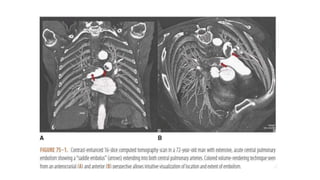

Classification of pulmonary embolism

category presentation

Massive pulmonary embolism(5%-10%) Systolic blood pressure<90 mm hg or poor tissue

perfusion or multisystem organ failure plus extensive

thrombus, such as “saddle” PE or right or left main

pulmonary artery thrombus

• CT Pulmonary Angiography

Classification of pulmonaryembolism category presentation Massive pulmonary embolism(5%-10%) Systolic blood pressure<90 mm hg or poor tissue perfusion or multisystem organ failure plus extensive thrombus, such as “saddle” PE or right or left main pulmonary artery thrombus Submassive pulmonary embolism(20%-25%) Haemodynamically stable but moderate or severe right ventricular dysfunction or enlargement, coupled with biomarker elevation indicative of right ventricular microinfarction and/or right ventricular pressure overload Small to moderate pulmonary embolism(70%) Normal haemodynamics and normal right ventricular size and function